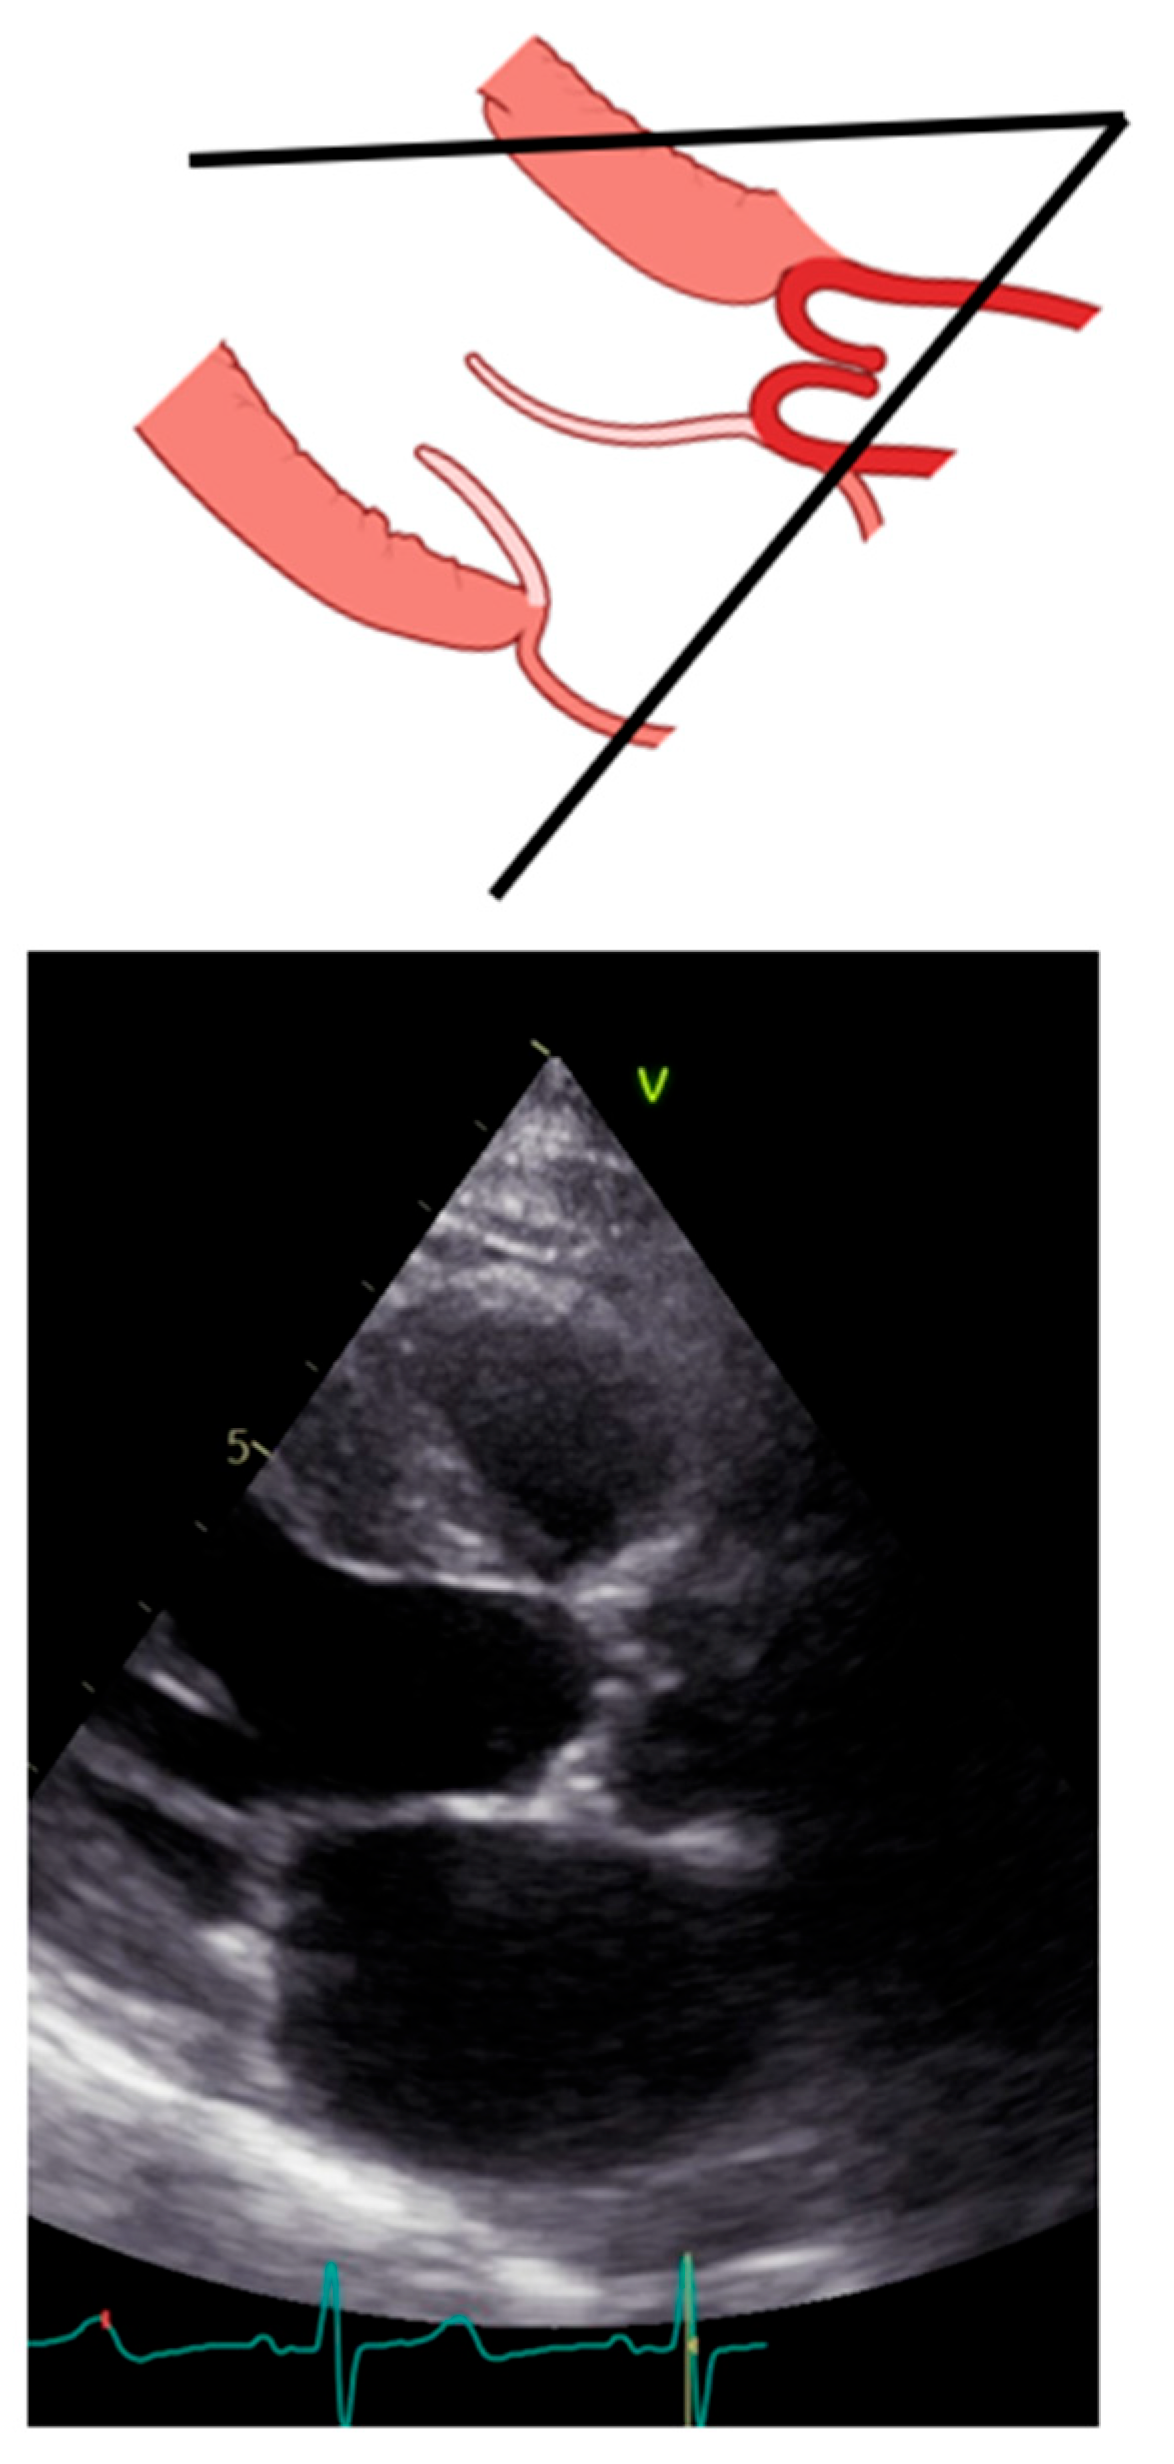

When assessing patients with aortic prosthesis, documentation of the size and type of valve should be marked on all echocardiograms. In addition, it is important to know, often for the aortic prosthesis, the level at which the prosthesis has been implanted: intra-annular, partially supra-annular, or wholly supra-annular. These aspects are important, since each valve type and size have their own normal ranges of values, such as peak velocity, peak gradient, mean gradient, and aortic valve effective orifice area (EOA). If repeat echocardiograms are being performed on a patient that has a prosthetic AV, the prior echocardiogram report should be reviewed to see what the AV measurements were, so any changes in function or abnormalities can be caught. To study aortic prosthesis, we will apply the same approach and calculations as we applied for a native valve. The prosthesis should be imaged from multiple views, with particular attention to (1) the opening and closing motion of the moving parts of the prosthesis (leaflets for bioprostheses and occludes for mechanical prostheses), (2) the presence of leaflet calcifications or abnormal echo density attached to the sewing ring, occluder, leaflets, stents, or cage, and (3) the appearance of the sewing ring, including careful inspection for regions of separation from the native annulus and for abnormal rocking motion during the cardiac cycle [50]. An important difference between the native aortic valve and prosthesis relies on the LVOT assessment. The LVOT diameter should now be measured at the ventricular side of the prosthesis, from outer edge to outer edge of the stent or ring just below the sewing ring for surgical prostheses or the stent for transcatheter bioprostheses [51] (Figure 11).

Figure 11. Correct measurement of left ventricular outflow tract in a patient with trans-catheter aortic valve implantation. Left: scheme of a left ventricular outflow tract. Right: a long-axis view with the implanted bioprostheses.